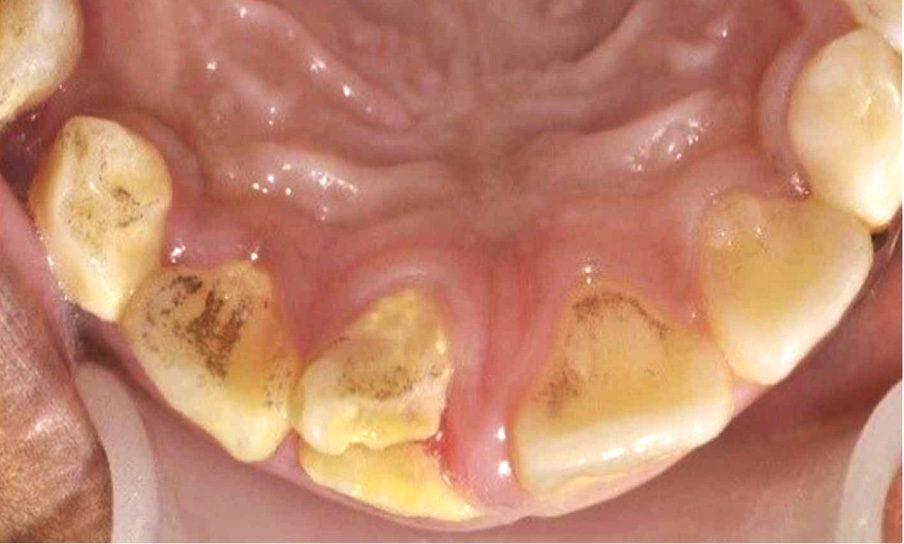

Streszczenie: Powikłane złamania koronowo-korzeniowe stanowią niewielki odsetek urazowych obrażeń zębów u dzieci; jednak leczenie tych urazów może być dla lekarzy poważnym wyzwaniem. Na rodzaj podejmowanego leczenia i jego wyniki pewien wpływ mogą mieć czynniki takie jak: złożoność urazu, wiek pacjenta i dojrzałość uzębienia, współpraca pacjenta oraz wymagania rodziców. U niektórych dzieci tego rodzaju obrażenia mogą wywierać znaczący wpływ na jakość życia. Celem niniejszej pracy jest opisanie dwóch przypadków powikłanego złamania koronowo-korzeniowego, skutecznie leczonych metodą odcinkowej ekstruzji ortodontycznej za pomocą aparatu stałego. Opisano podstawy takiej metody leczenia i jej pozytywne wyniki, podkreślając jej zalety i wady.

Spośród różnych rodzajów urazów zębów najczęściej opisywane jest złamanie korony, które stanowi jedną trzecią urazów. Natomiast złamania koronowo-korzeniowe stanowią jedynie 0,3-5% stwierdzanych obrażeń [5]. Złamanie koronowo-korzeniowe jest to złamanie [...]